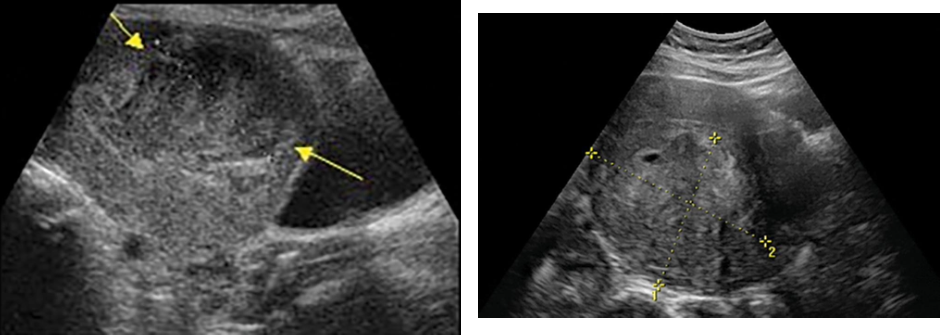

Sonographic Findings

Endometriosis may appear as bilateral or unilateral ovarian cysts with patterns

ranging from anechoic to solid, depending on the amount of blood and its

organization (Fig. 44.19).

Sonographic Appearance

➢ Well-defined unilocular or multilocular

➢ Predominantly cystic mass containing

➢ Diffuse homogeneous, low-level internal echoes (Fig. 44.20).

➢ Occasionally a fluid-fluid level can be seen.

➢ Small linear hyperechoic foci may be present in the wall and are thought to be

cholesterol deposits accumulating in the cyst wall.